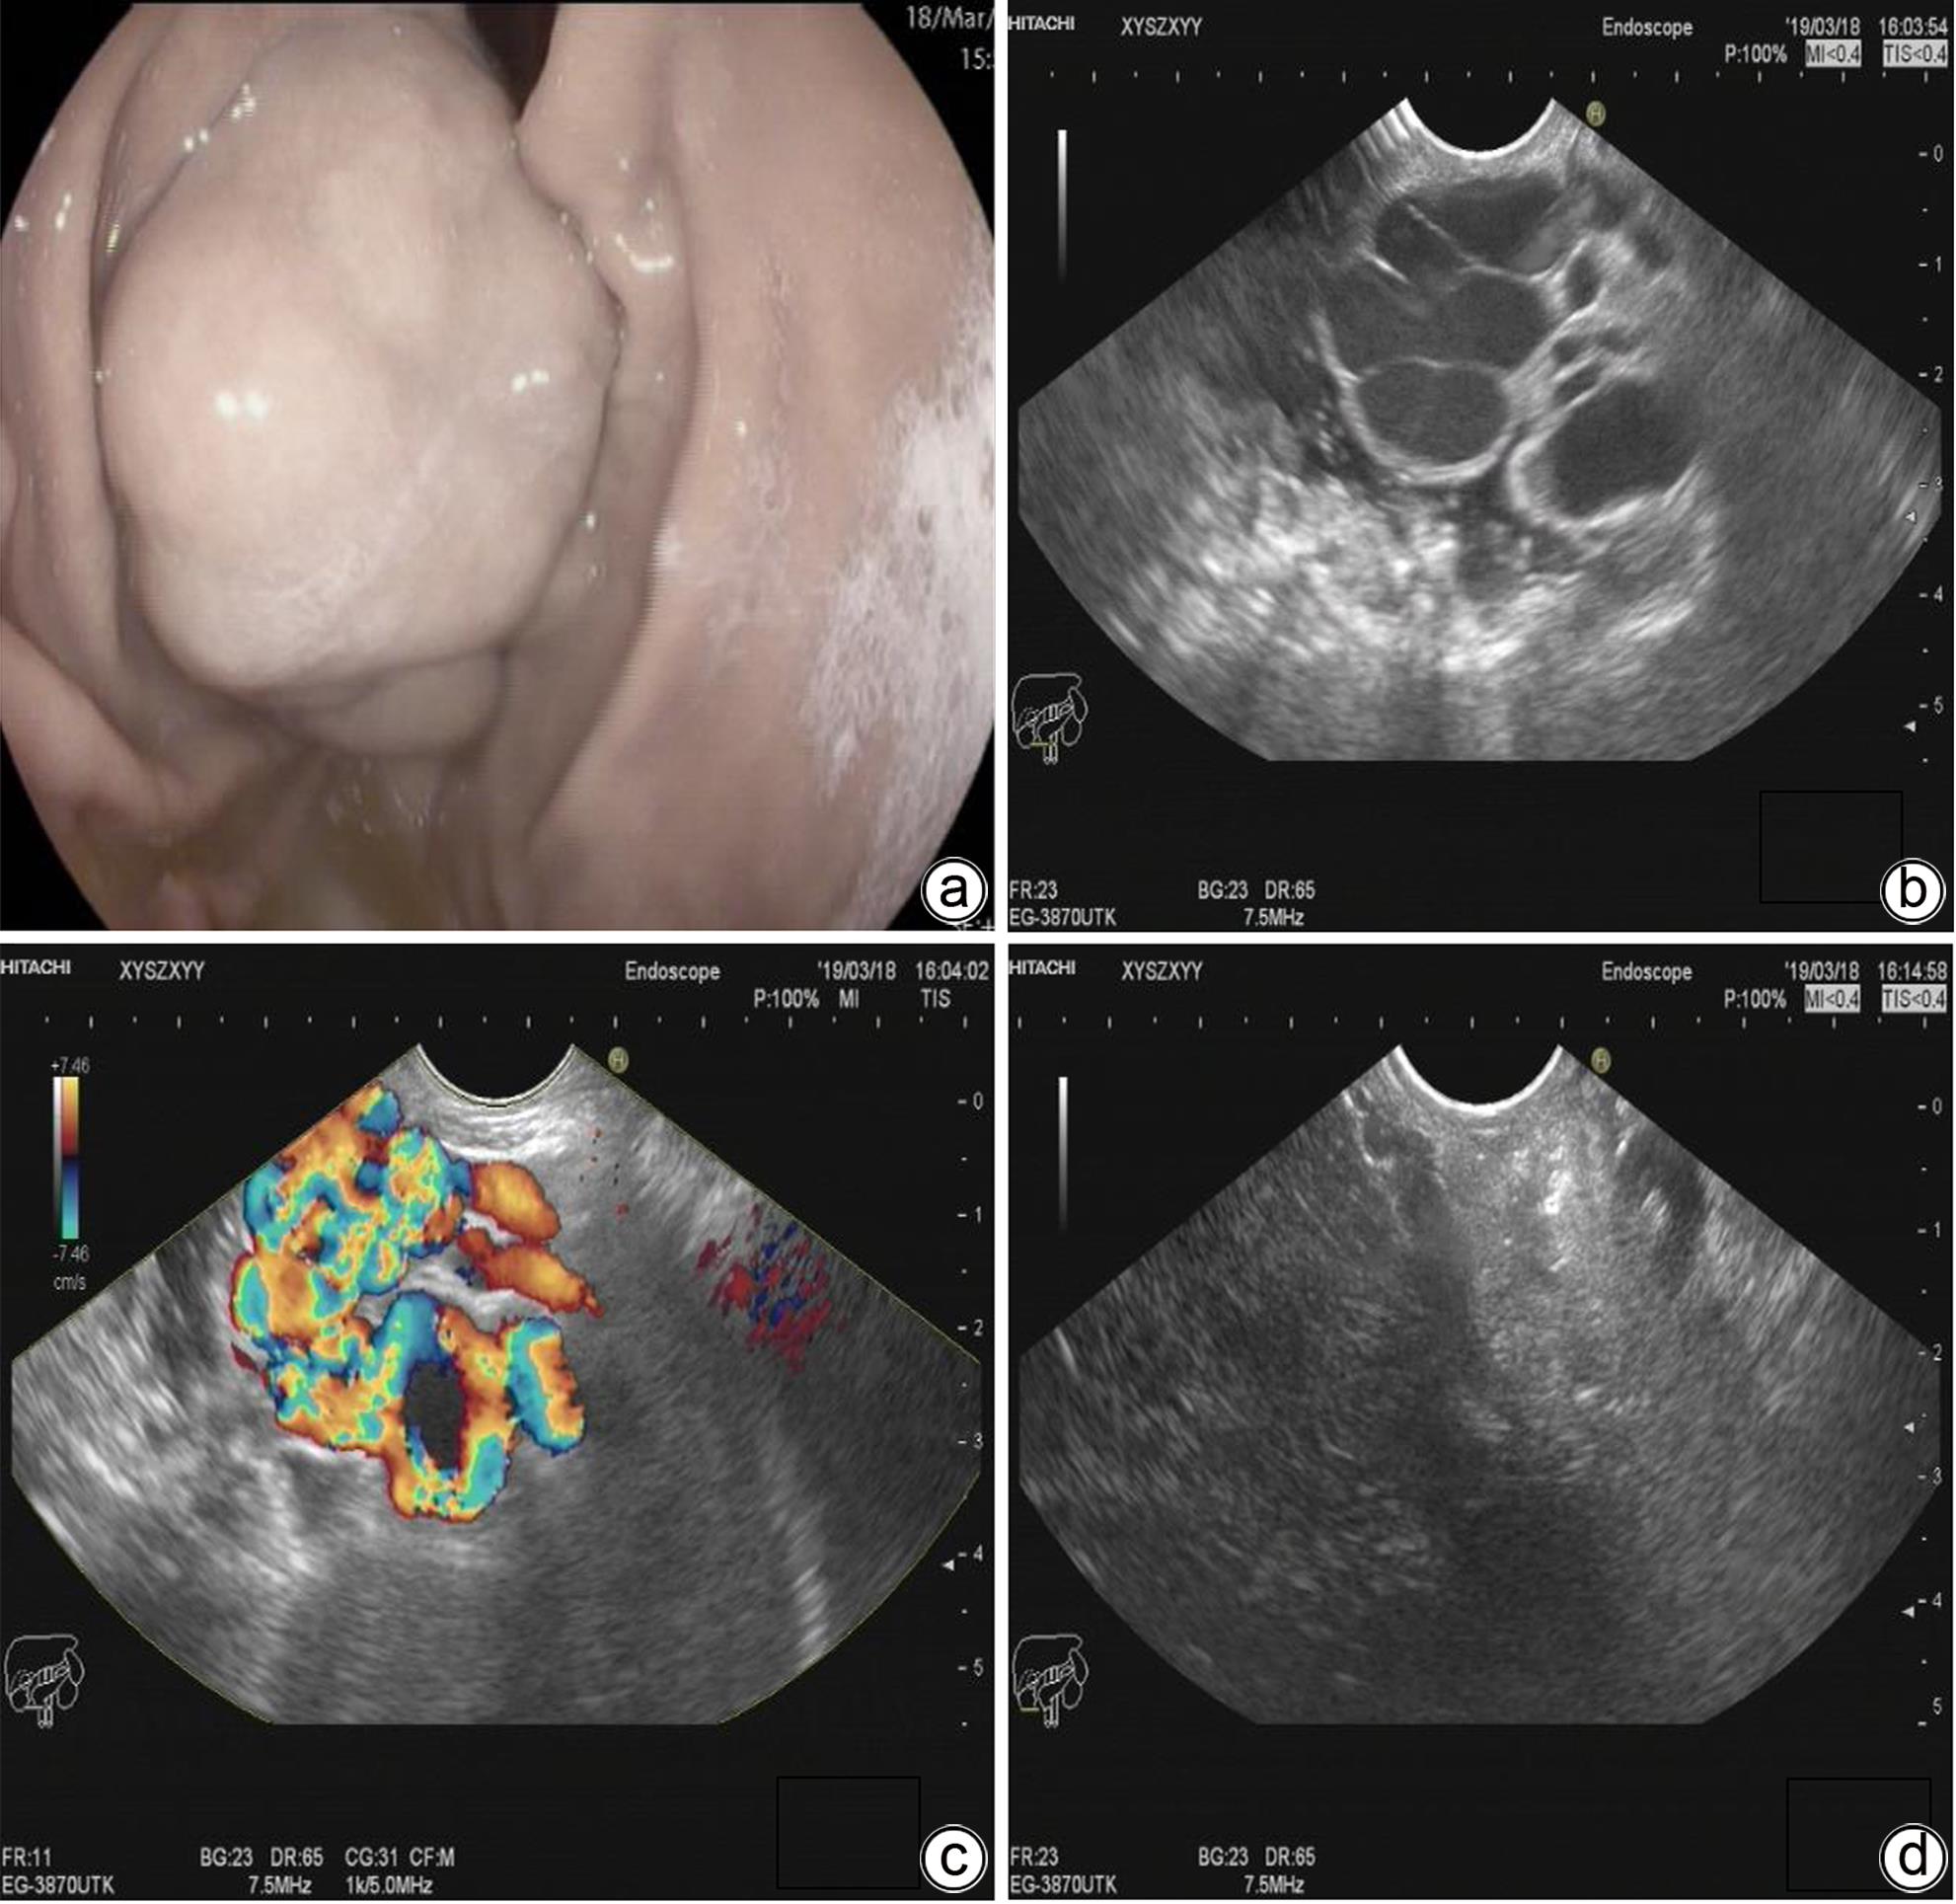

金属夹辅助内镜超声引导组织胶注射治疗合并胃肾分流的肝硬化胃静脉曲张患者的效果初探

马佳丽, 艾正琳, 胡居龙, 蒋煜, 周玉玲, 梁秀霞, 魏红山, 李坪

2024, 40(4): 734-738. DOI: 10.12449/JCH240415

摘要(1108) HTML (309) PDF (1036KB)(60)

摘要:

目的  探讨金属夹辅助内镜超声引导组织胶注射治疗合并胃肾分流的胃静脉曲张患者的效果及安全性。  方法  纳入2023年2月—2023年6月因肝硬化伴胃静脉曲张于首都医科大学附属北京地坛医院就诊,证实存在胃肾分流(GRS),并接受金属夹辅助内镜超声引导组织胶注射治疗的患者。主要的评价指标是术后曲张静脉减轻或消失情况,次要评价指标为手术完成情况及并发症。  结果  共11例合并GRS的胃静脉曲张患者纳入研究,男7例,女4例;中位年龄55岁;肝功能Child-Pugh A级1例,Child-Pugh B级7例,Child-Pugh C级3例;分流道最大直径(中位)8 mm,最小直径(中位)4 mm。治疗前靶血管血流中位流速11 cm/s,金属夹阻断后靶血管中位流速5 cm/s;中位组织胶使用量2 mL,聚桂醇使用量均为1 mL。所有患者手术结束后血流信号100%消失,手术成功率100%。随访6周患者均无再出血发生。术后1个月复查胃镜示静脉曲张根除或基本消失9例,静脉曲张改善2例。  结论  对于合并GRS的胃静脉曲张肝硬化患者,金属夹辅助内镜超声引导组织胶注射治疗是一种可行,安全,有效的方法。